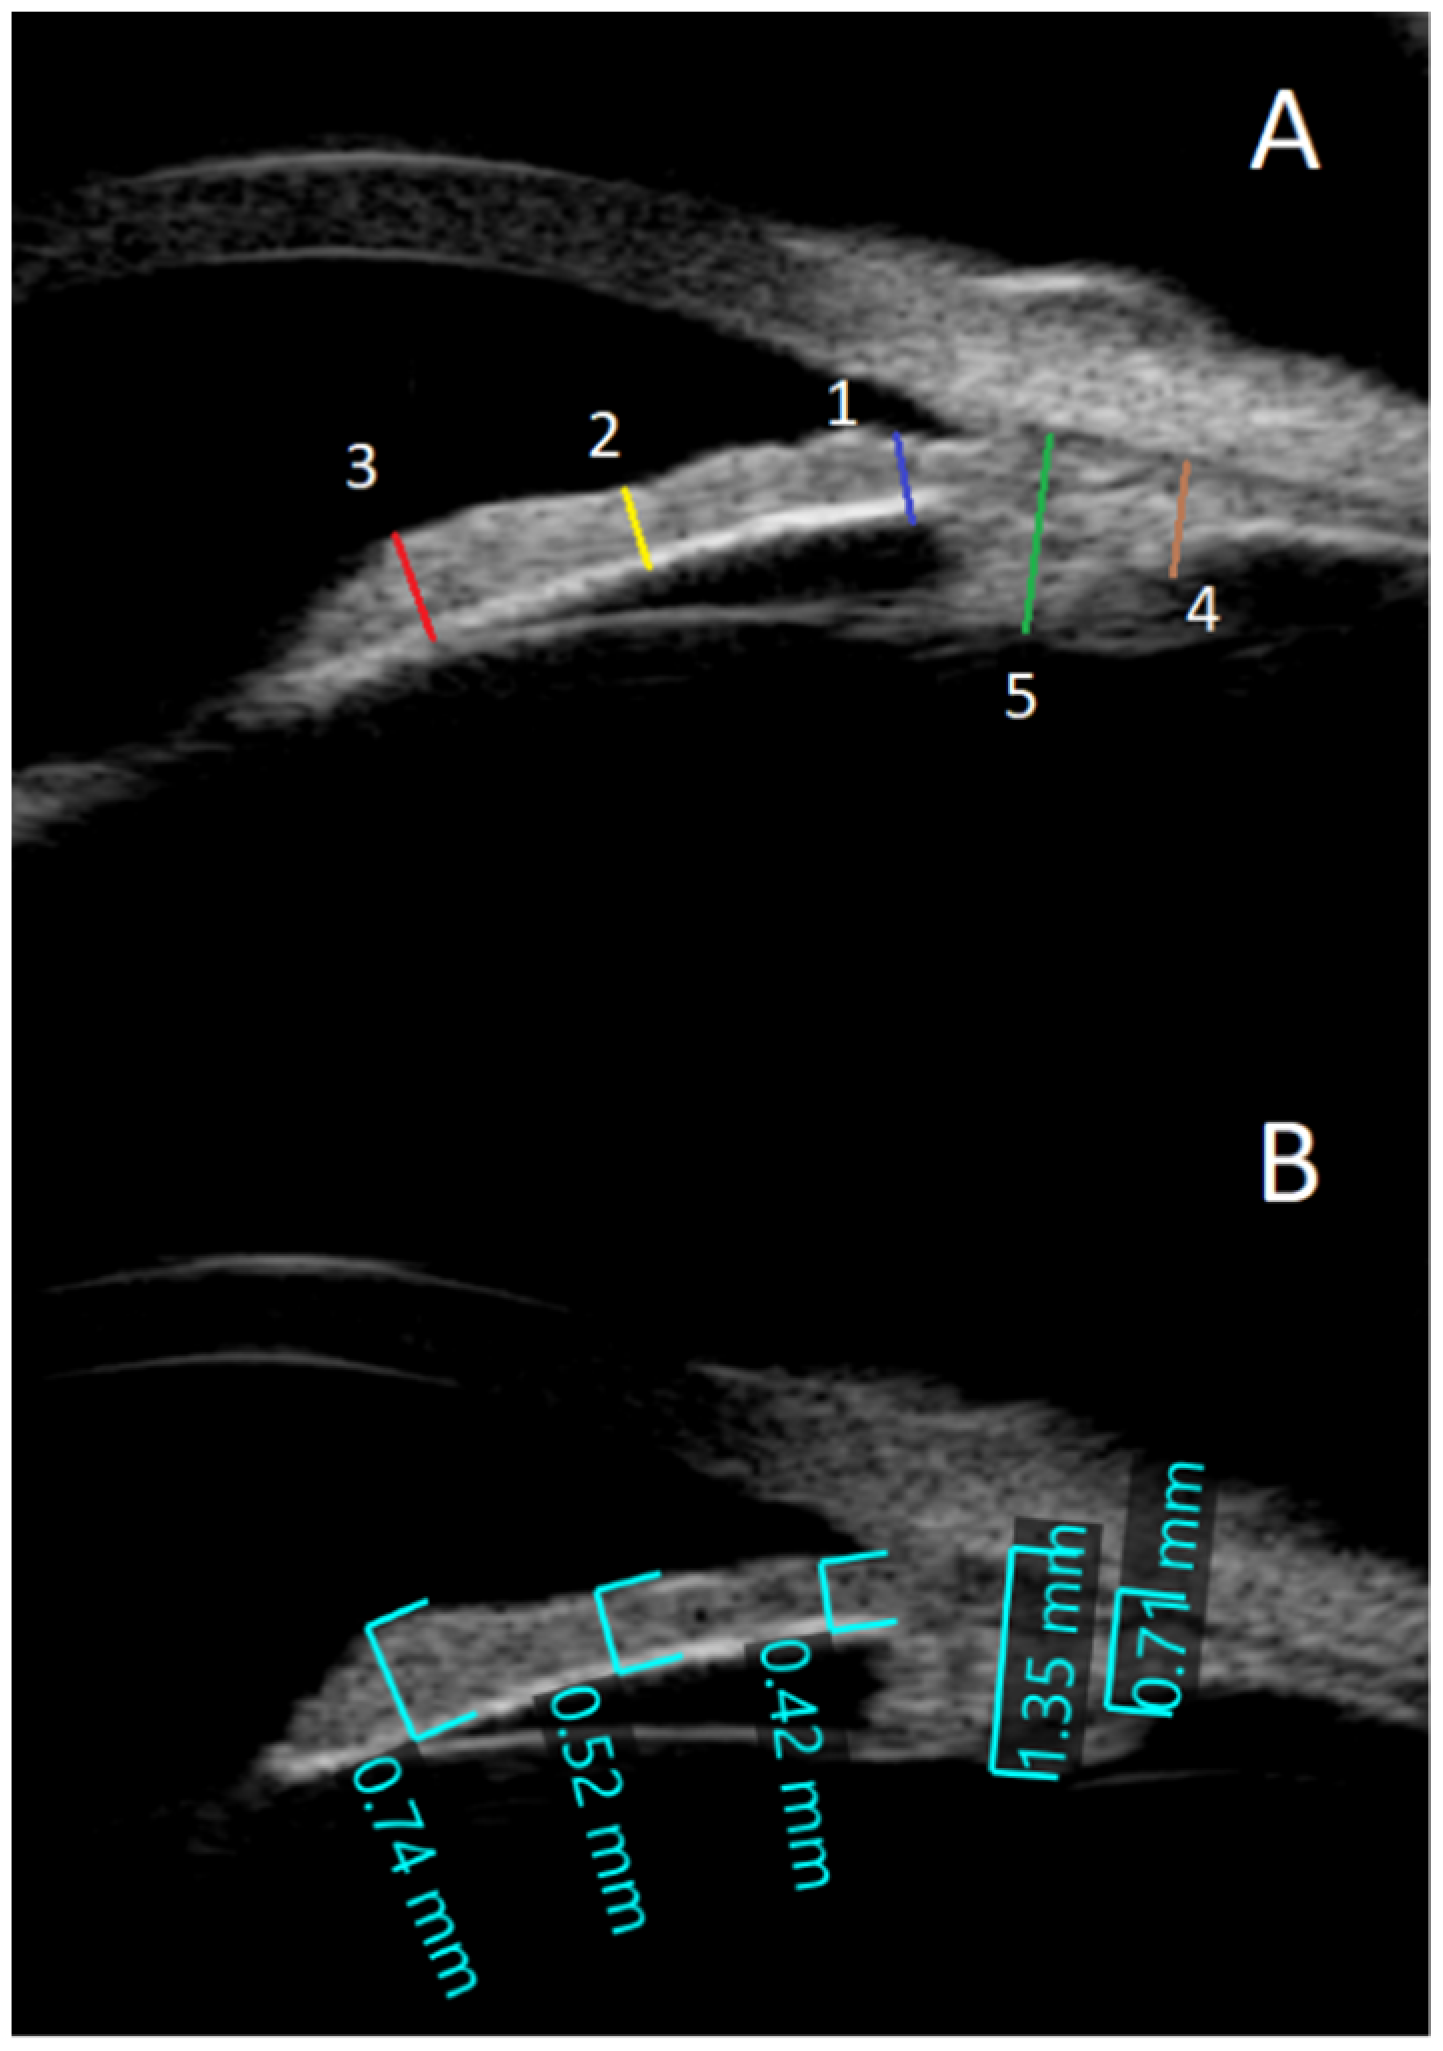

- The anterior chamber angle (in degrees) was calculated using two 0.5 mm lines that began at the iris root and traveled across the posterior cornea and the anterior surface of the iris (Figure 1B). Images were obtained from each quadrant (upper, lower, nasal, and temporal).

- To determine the anterior segment depth (ASD), the axial distance between the anterior corneal surface and the anterior surface of the lens was measured; views were as vertical as feasible, as indicated on the screen (See Figure 1B).

- The thicknesses of the iris were measured at 0.8 mm from the iris root, amid the iris, and at the juxtapupillary edge of the iris (thickest area of the iris at 1 mm distance from the pupil).

- The perpendicular distance between the apex of the ciliary body (inner tip) and the inner wall of the sclera was measured to assess CB thickness. The distance between the inner-most point of the ciliary process and the inner wall of the sclera was used to calculate the CB + ciliary process thickness (perpendicular to the scleral wall).